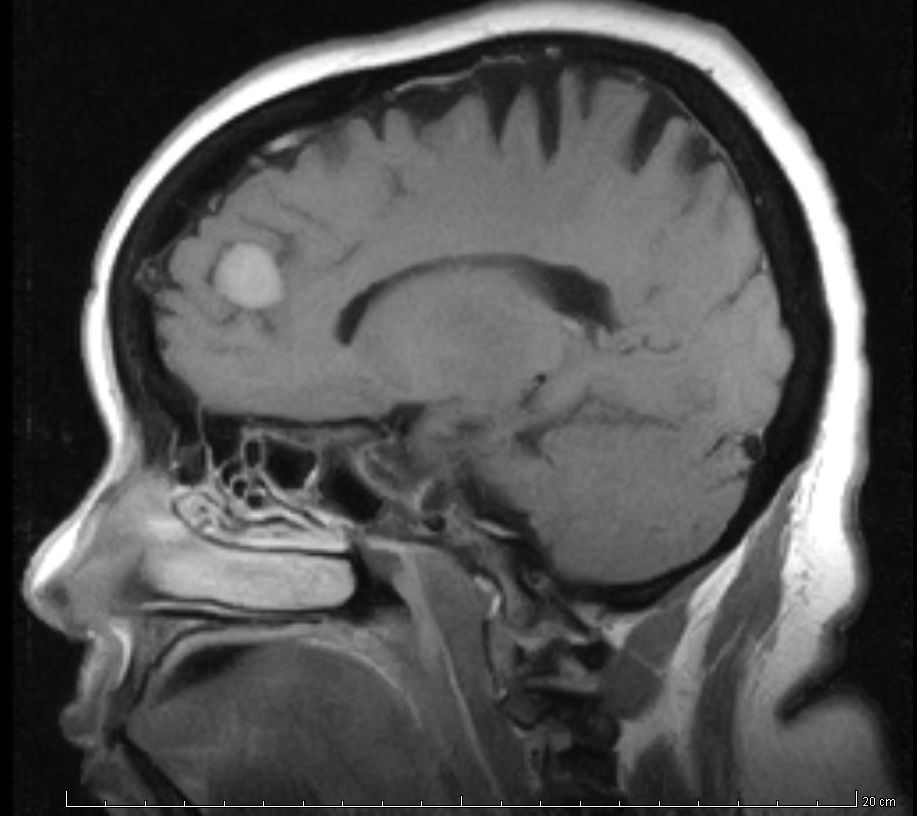

Hallazgos incidentales en la resonancia magnética cerebral de niños

19 octubre 2017